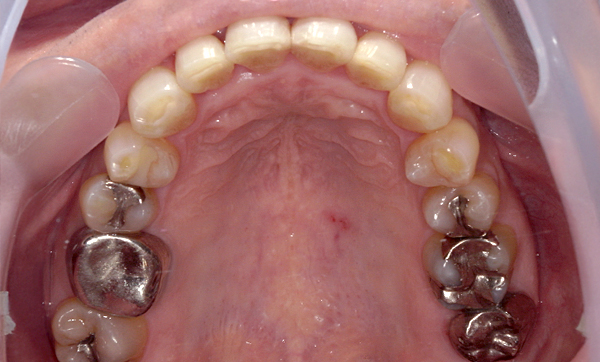

症例_008 「上下の前歯」症例

治療期間:13ヶ月金額:57万円+税40代女性捻転歯前歯のガタガタ

Before | After |